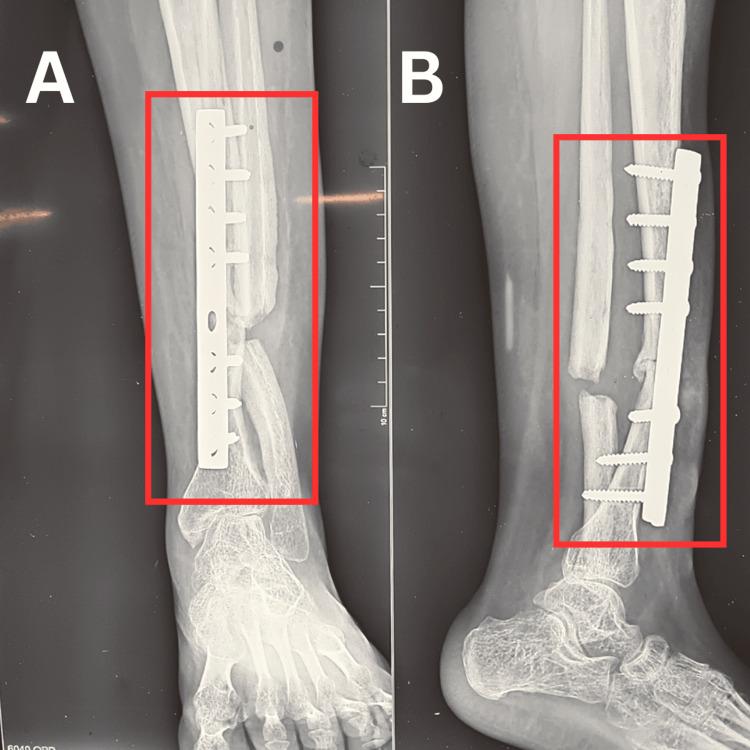

Pseudoarthrosis of the tibia is an uncommon condition that occurs due to non-union of bone and typically requires surgery. It may cause fractures that develop spontaneously or after minor trauma. Physiotherapy is an excellent treatment for this uncommon condition. The tibia of the affected limb becomes malformed and bends backwards. This case report outlines the interdisciplinary programme adopted to successfully manage a 23-year-old female patient with right-sided tibial pseudoarthrosis. Following the implantation of Ilizarov's external fixator to correct the deformity, the patient was referred to the physiotherapy department for post-operative management. After the implementation of a tailor-made physiotherapy protocol focusing on proprioceptive retraining, significant improvements were seen in her joint proprioception, muscular strength and range of motion.

胫骨假关节是一种因骨不连而发生的罕见病症,通常需要进行手术。它可能导致自发性骨折或轻微创伤后骨折。物理治疗是治疗这种罕见病症的一种有效方法。患肢的胫骨会发生畸形并向后弯曲。本病例报告概述了为成功治疗一名患有右侧胫骨假关节的23岁女性患者而采用的跨学科方案。在植入伊利扎罗夫外固定器以矫正畸形后,患者被转至物理治疗科进行术后管理。在实施了以本体感觉再训练为重点的量身定制的物理治疗方案后,她的关节本体感觉、肌肉力量和活动范围都有了显著改善。